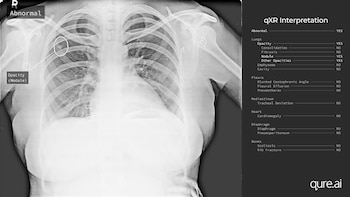

En menos de un minuto, una nueva aplicación de celular o computadora puede escanear una radiografía en busca de síntomas de tuberculosis, COVID-19 y otras 27 enfermedades.

Hace algunos meses, ambos nosocomios comenzaron a usar qXR, una aplicación creada por la empresa india Qure.ai y subsidiada por el gobierno indio. La aplicación le permite al usuario escanear una radiografía. Si encuentra evidencia de tuberculosis, le asigna una calificación de riesgo al paciente. Los doctores pueden realizar pruebas de confirmación a los pacientes con el riesgo más alto.

En estudios realizados por Stop TB Partnership para comparar diferentes aplicaciones de inteligencia artificial, todas las aplicaciones de inteligencia artificial tuvieron mejores resultados que las interpretaciones humanas, y al parecer el desempeño de la qXR fue el mejor.

La aplicación identifica la tuberculosis con una precisión del 95 por ciento, según el director ejecutivo de Qure.ai, Prashant Warier. Sin embargo, ese nivel de precisión no está basado en condiciones reales, “un problema común” en las aplicaciones basadas en inteligencia artificial, según Topol. Un programa para detectar tuberculosis podría ser menos preciso en Estados Unidos y Europa del Este que en India, porque la prevalencia de la enfermedad es más baja en esos lugares, agregó Topol.